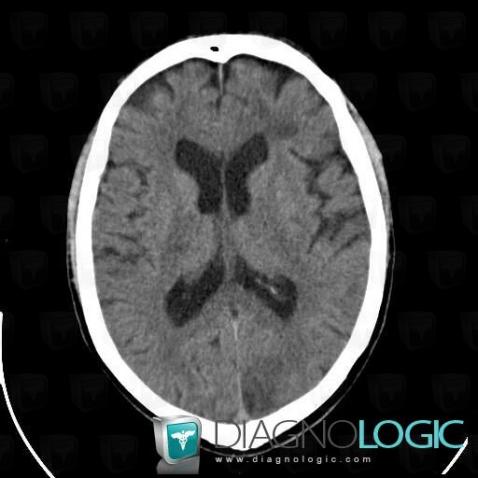

Cerebral infarction, Cerebral hemispheres, CT

Here is the specific information in the key image above:

- Diagnosis Cerebral infarction, Location(s) Cerebral hemispheres, with gamuts Hypodense intracerebral lesion on noncontrast CT